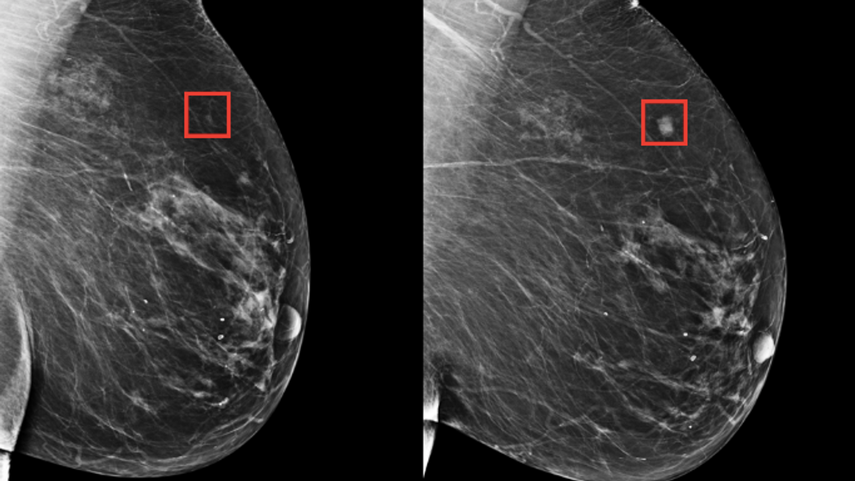

En base a ese conocimiento previo, un equipo de investigadores liderados por el patólogo Lee Cooper de la Facultad de Medicina de la Universidad Northwestern ha diseñado una herramienta, mediante IA, que evalúa el tejido del cáncer de mama a través de imágenes digitales que ofrecen un enorme detalle del aspecto que presentan las células cancerosas y no cancerosas, así como de las interacciones entre ellas.

La herramienta creada mediante IA analiza 26 propiedades diferentes del tejido mamario de una paciente para generar una puntuación pronóstica global.

El sistema también genera puntuaciones individuales para las células cancerosas, inmunitarias y estromales (células madre adultas) para explicar de donde procede la puntuación global al patólogo.